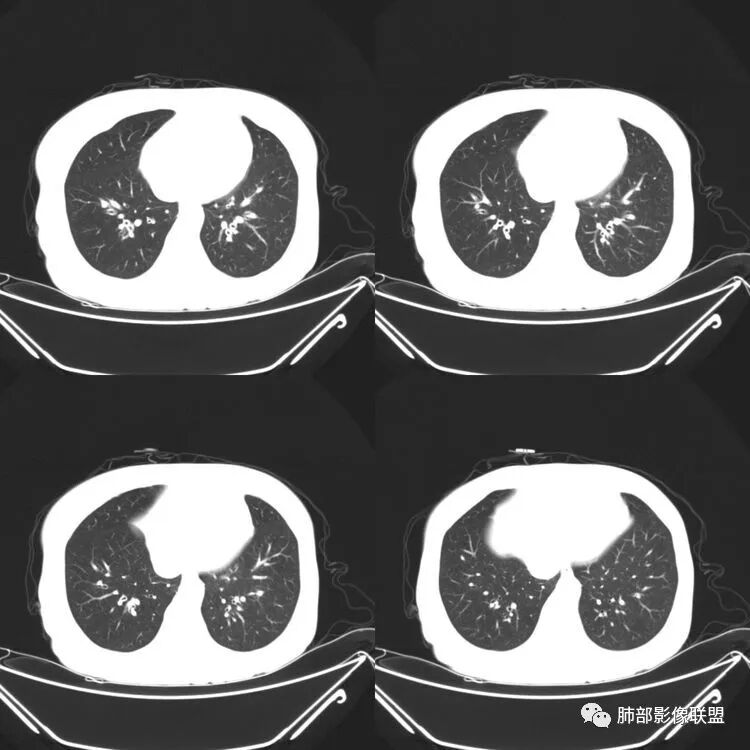

患者,女,64岁,反复咳嗽、咳痰、胸闷10年,加重2周患者10余年来每当受凉感冒出现咳嗽、咳痰、胸闷,有时痰中带血,输液治疗(具体不详)可好转。既往有声带肥厚手术病史。CT示气管、主支气管及分支支气管管壁弥漫性增厚累及膜部,局部伴钙化,管腔狭窄,考虑淀粉样变性

老年女性,慢性病程急性起病,主支气管及各级分支弥漫性不均匀性增厚,管壁钙化,管腔狭窄,累及膜部,考虑淀粉样变性,鉴别复发性多软骨炎,气管支气管骨化症,侵袭性曲霉菌病

气管及支气管管壁弥漫性增厚,累及膜部,局部伴钙化,管腔狭窄,局部管壁结节样增厚,不规则狭窄,考虑淀粉样变性,鉴别复发性多软骨炎,WG

患者,女,64岁,反复咳嗽、咳痰、胸闷10年,加重2周。气管支气管及两肺下叶 支气管弥漫性的环状增厚,管腔扩张,管腔感觉比较松弛。第一感觉,气管支气管淀粉样变。鉴别诊断,1、支气管内膜结核,肺内散在一些支气管的播散病灶,粟粒结节为主,形态比较单一。2、复发性的多软骨炎,就得了解一下其他部位,有没有多个部位的软骨炎。这个病人右侧胸廓缩小,升主动脉明显的扩张,其横径明显的超过了降主动脉。

南边:肺部有肺气肿支气管腔狭窄淀粉样变性?复发性多软骨炎?血管炎?慢支?结核?曲霉菌?南边:一般还是淀粉样变性与复发性多软骨炎鉴别其次就是支气管骨化症,但是骨化下朝上,且壁结节状钙化明显,本例不太支持。至于结核、曲霉菌?1.结核,一般不会这么广泛,支气管壁狭窄后扩张2.曲霉菌可以这么广泛,但是支气管壁管腔扩张,而且附近脂肪间隙有炎性反应,不太支持;3.血管炎,一般合并肺内有病灶,但是声带受累,放待排;4.软骨炎一般全身受累,例如耳廓等;而且膜部不受累,不太支持;倾向于淀粉样变性;淀粉分很多型,气管支气管是最常见的。尘缘:影像上生理性钙化与支气管骨化无法区别,镜检也不好鉴别,需要依赖活检,看粘膜中是否合并炎性改变(淋巴细胞,组织细胞等炎性细胞侵润)来鉴别Coke with ice:经常看到的这种是老年性肺改变,又称年龄相关肺改变。气管和支气管弥漫性软骨钙化,常见老年女性。尘缘:支气管骨化症很罕见的,所以绝大多数还是生理性钙化。对于老年人,无临床症状的钙化,还是基本上都是生理性钙化,无临床意义。大雄:如果管壁钙化伴明显增厚 影像还是提示一下建议支气管镜稳妥些

三、影像表现

1.气管支气管型

①气管支气管壁增厚,形成粘膜下斑块与结节

②管腔广泛狭窄、闭塞

③管壁钙化

④膜部受累(具有重要鉴别意义)